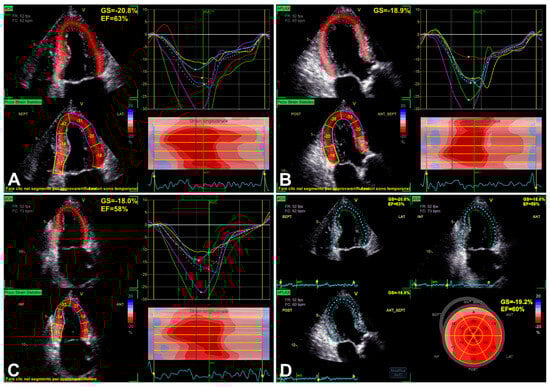

3.1. Left Ventricular Global Longitudinal Strain